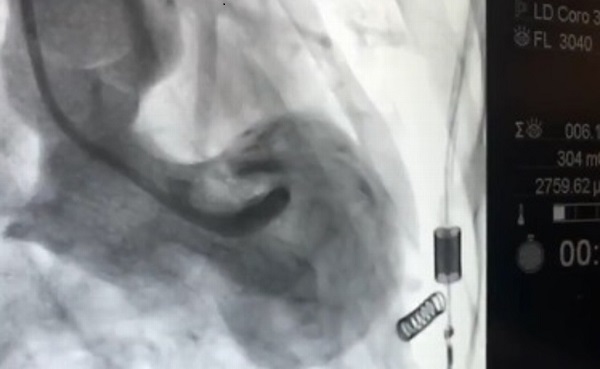

Agregó que en la imagen del “Síndrome del corazón roto” se aprecia la cardiomiopatía de TakoTsubo, que generalmente presenta la forma de un jarrón japonés para sacar pescado, es una afección cardíaca causada por estrés, es un infarto que en realidad no es un infarto, sino la irrupción súbita de hormonas ante la presencia de un estrés o una fuerte impresión.